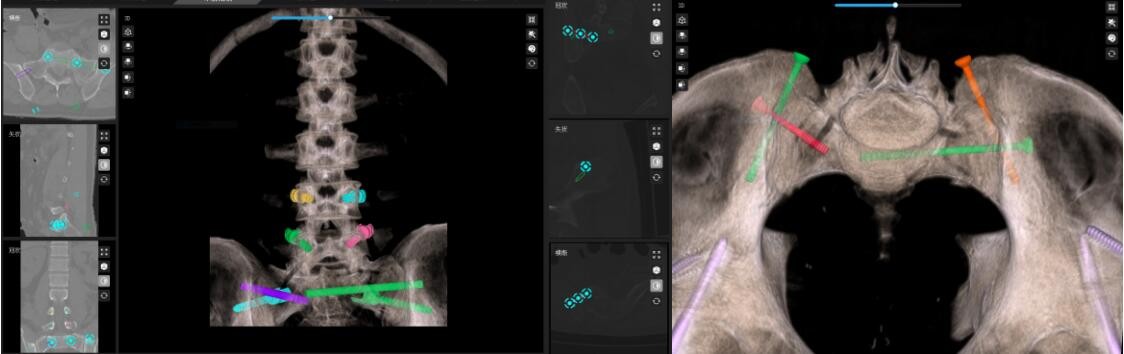

术前,叶军博士将患者的骨盆骶骨CT数据导入骨科机器人数字平台,进行三维重建和精准分析。通过数字化技术,医生能够清晰看到骶骨骨折移位及骶前孔受压的具体情况:骶骨体骨折塌陷,左侧骶骨翼受侧方挤压,骶1骶前孔前方受碎骨块压迫。

2. 机器人辅助复位、骨科机器人“透视眼”

手术中,骨科机器人通过机械臂引导,精准定位并打入骨盆外固定架螺钉。随后,利用外固定架对骶骨骨折进行间接复位,成功扩大了左侧骶前孔的空间。这一操作不仅减少了手术创伤和出血量,还显著提高了手术效率。

*3D透视骨骼迷宫:第一时间输入CT数据至骨科机器人数字平台,3D重建精准锁定碎骨位置;

*路径规划:机器人自动计算最佳螺钉轨迹,避开血管神经密集区;

机械臂精准植入:用可调节外固定架实现"无创复位",瞬间扩大被压神经孔 。

术后:第一次手术,骨科机器人辅助,骨盆外固定,闭合复位,骶神经孔减压。

二次手术规划:腰椎骨盆固定及骶骨翼骶骨螺钉固定。